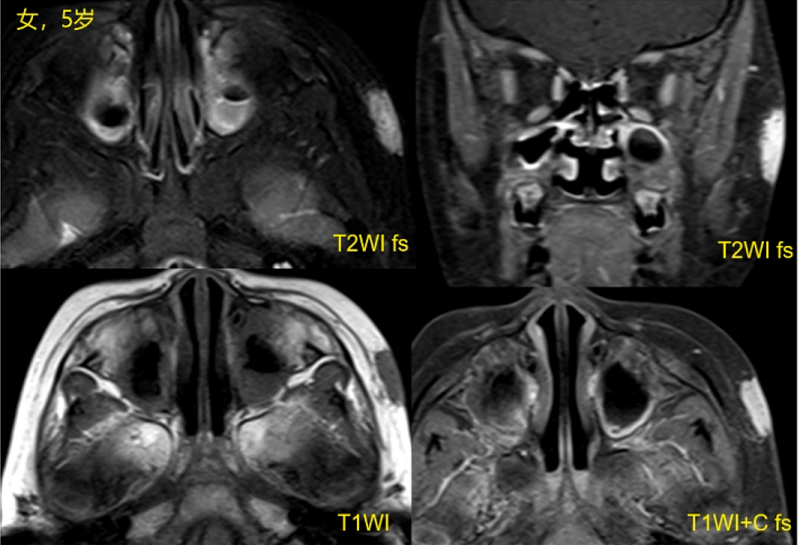

大多数血管瘤可以诊断,无需额外检查。但如果血管瘤位置深,则难以通过肉眼与其他血管畸形或肿瘤相区别,需借助影响学检查(如图5、图6)。如果仍不能确诊,还需要行皮肤活检。

▲ 图6 磁共振检查